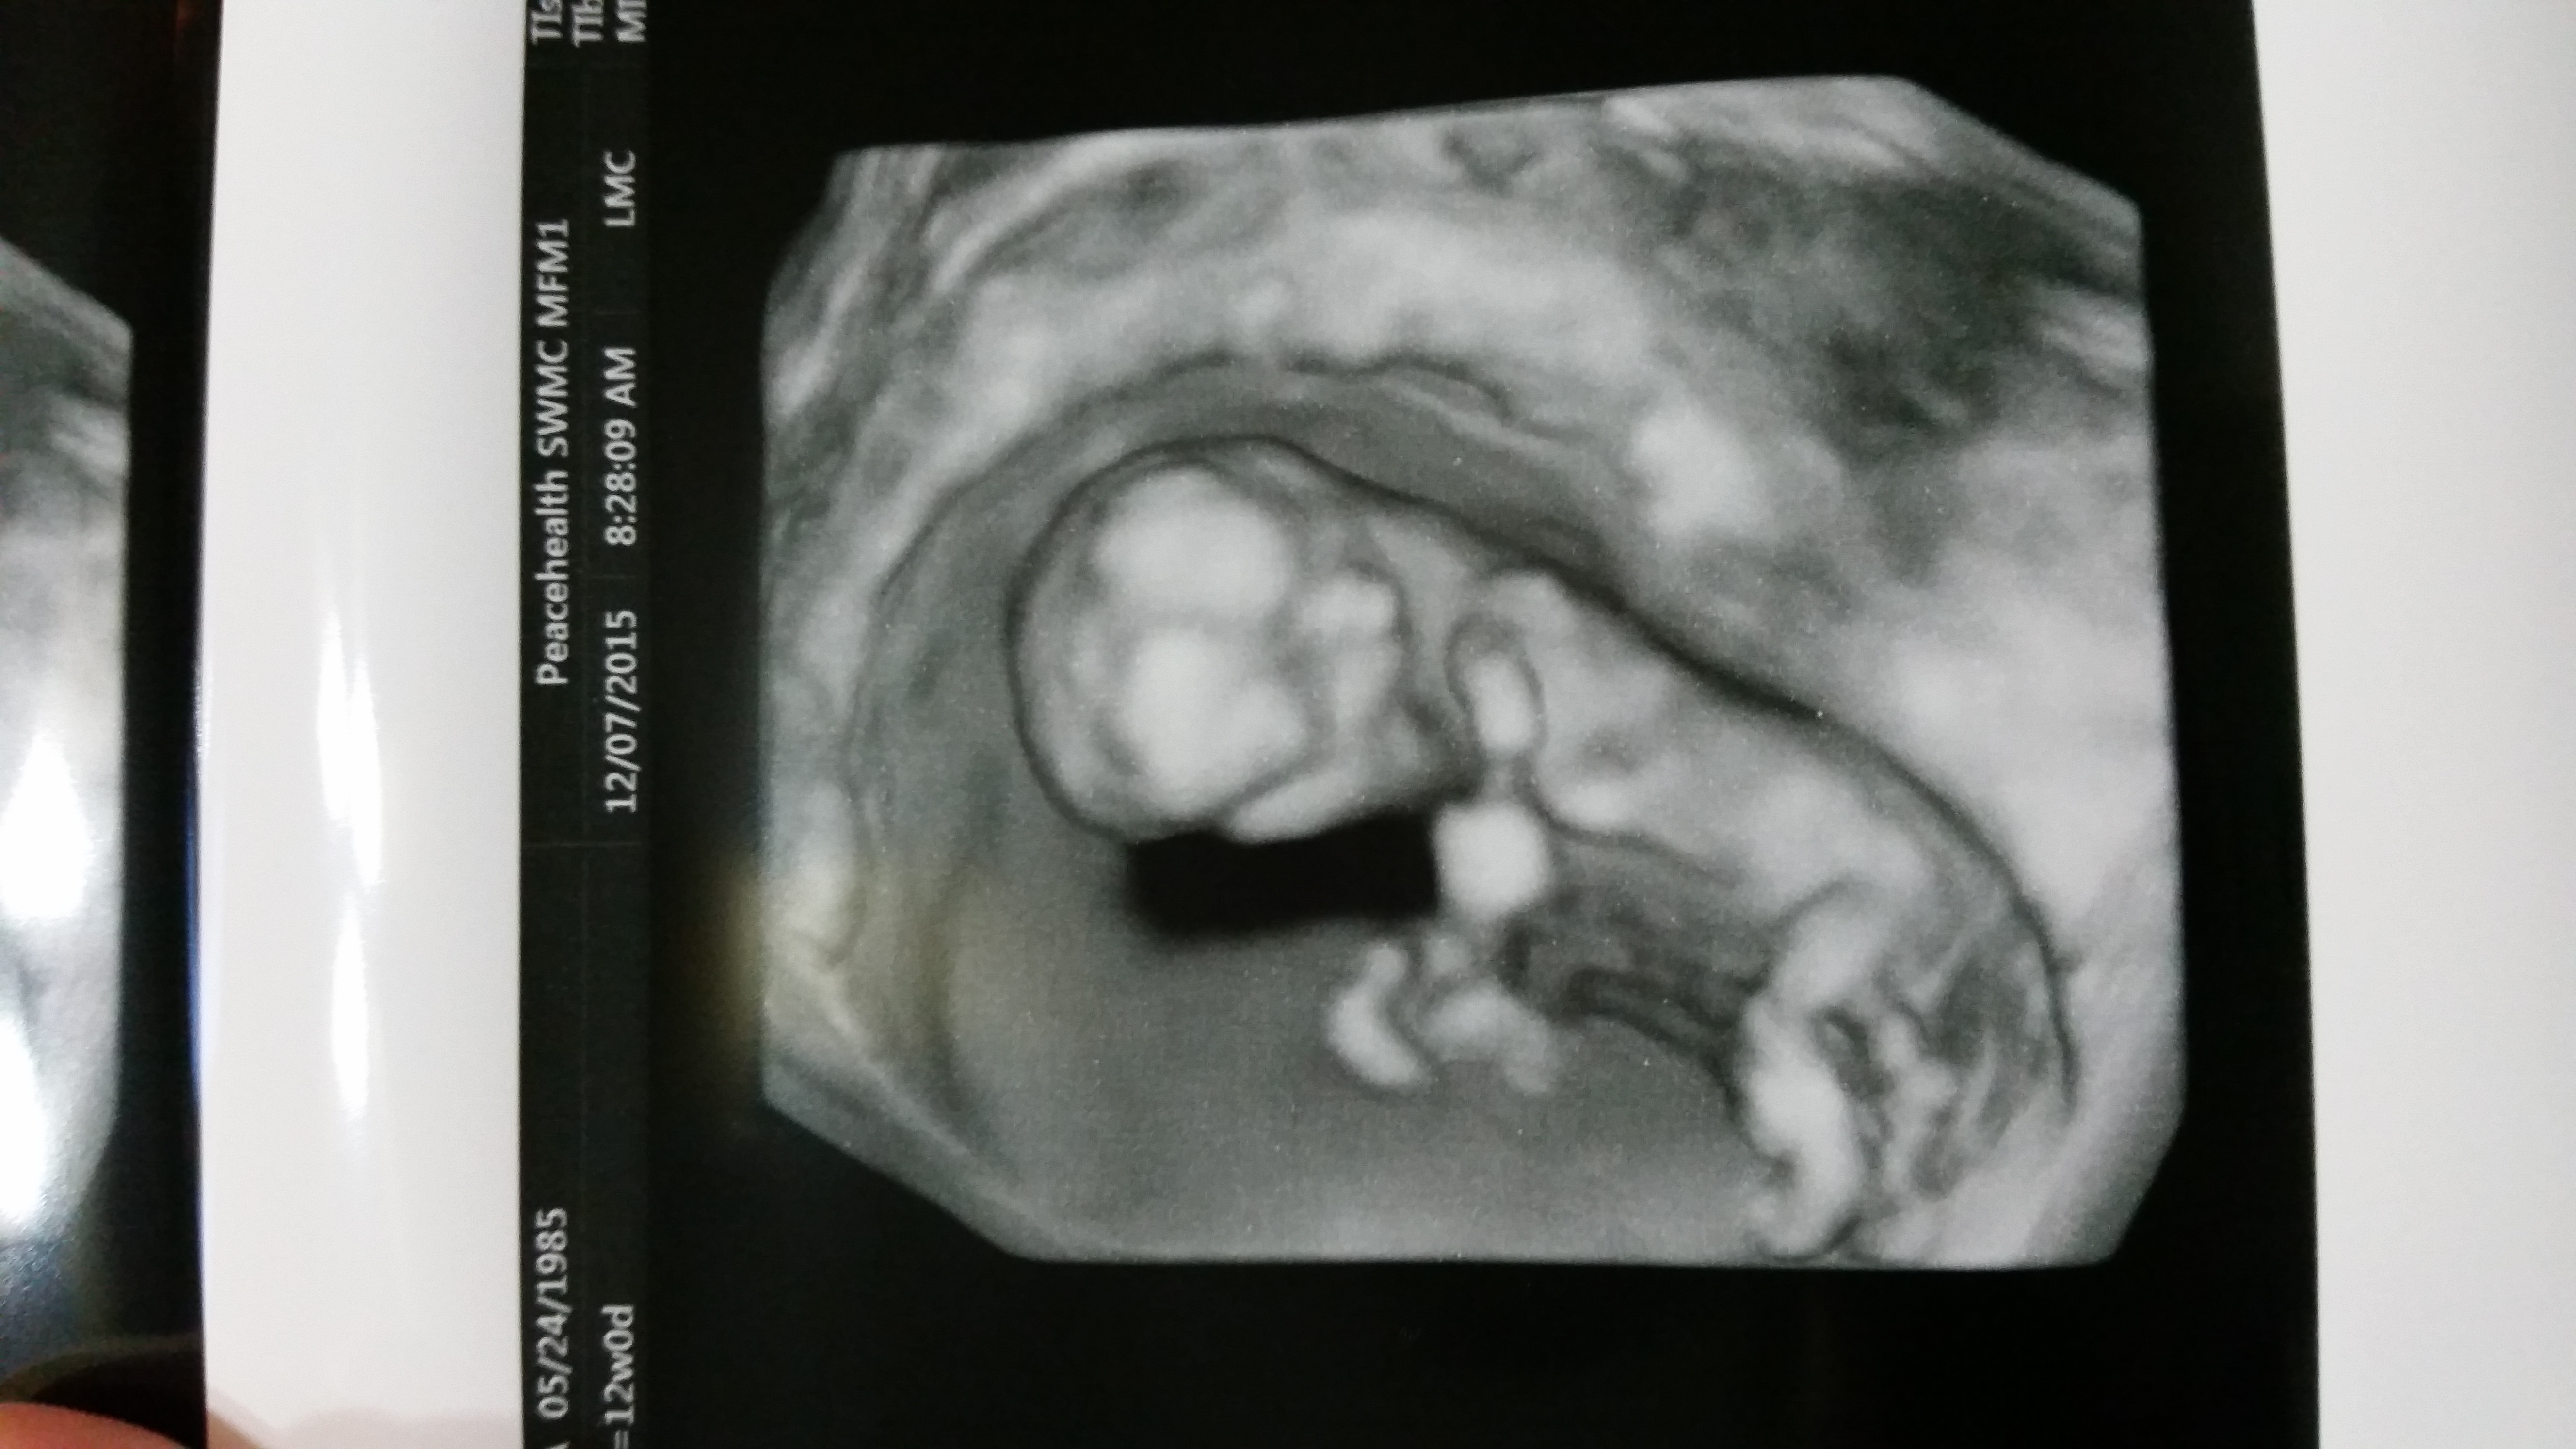

Had my NT scan today. Such a huge difference from my 7 week ultrasound. It actually had arms and legs this time!!

12w 1d